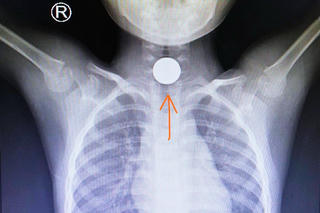

Mỗi dịp Tết đến, các đồ ăn như bánh, trái, thạch rau câu, hạt bí, hạt dưa... là những thứ mà hầu như gia đình nào cũng có. Tuy nhiên, các chuyên gia y tế lưu ý, với những gia đình có trẻ nhỏ, phải hết sức chú ý, nếu không trẻ sẽ dễ bị hóc, sặc khi ăn những thứ này. Hóc đường thở là một trong những tai nạn nguy hiểm nhất đối với trẻ em.